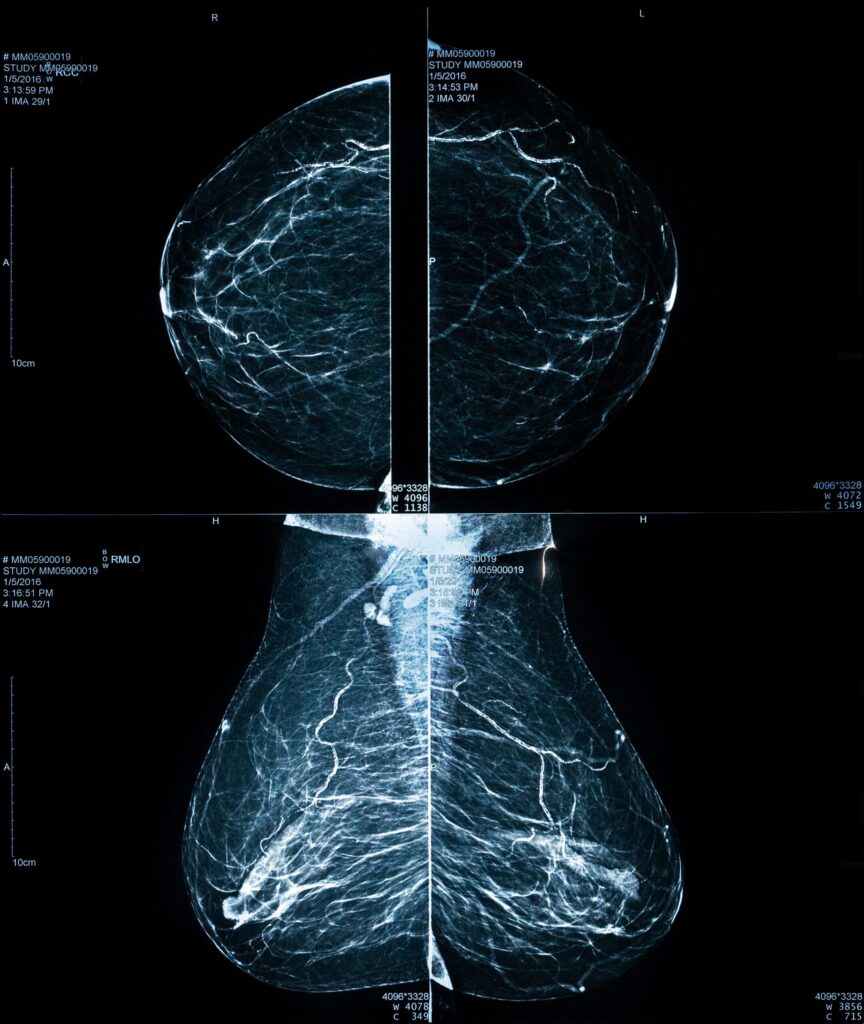

Quando falamos em “mamas densas”, significa que existe uma proporção maior de tecido fibroglandular (glandular e fibroso) em comparação ao tecido adiposo. É como se sua mama tivesse mais “estrutura” e menos gordura. Na mamografia, o tecido fibroglandular aparece branco, enquanto a gordura aparece escura (cinza).

A densidade mamária é identificada durante a realização da mamografia. O radiologista avalia cuidadosamente a quantidade de tecido fibroglandular presente nas imagens e classifica a mama em uma das quatro categorias estabelecidas pelo Colégio Americano de Radiologia (ACR):

Categoria A: Mamas Predominantemente Gordurosa. A maior parte do tecido é gorduroso, facilitando a visualização de alterações; Menos de 25% de tecido fibroglandular

Categoria B: Mamas com Densidade Fibroglandular Dispersa. Existem algumas áreas de tecido denso espalhadas, mas a maior parte ainda é gordurosa; Entre 25% e 50% de tecido fibroglandular

Categoria C: Mamas Heterogeneamente Densas. Há mais tecido denso do que gordura, o que pode dificultar a identificação de pequenos nódulos; Entre 51% e 75% de tecido fibroglandular

Categoria D: Mamas Extremamente Densas. A grande maioria do tecido é denso, tornando a mamografia um exame mais desafiador para a detecção de lesões; Mais de 75% de tecido fibroglandular

Mulheres nas categorias C e D são consideradas como portadoras de mamas densas.

- O “Efeito de Mascaramento”: Este é o desafio mais conhecido. Como o tecido denso e um possível nódulo aparecem brancos na mamografia, a densidade pode funcionar como uma “camuflagem”, escondendo lesões em estágios iniciais. É como tentar encontrar um urso polar em uma tempestade de neve: não é impossível, mas é mais difícil.